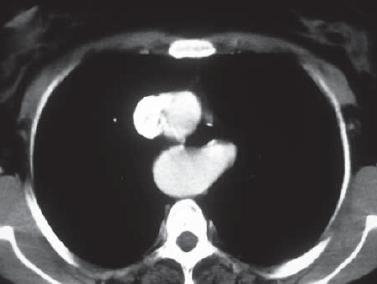

An initial upper endoscopy, an esophagogram, and an x-ray of the thorax were performed. The endoscopy showed no alterations, while the esophagogram showed lateralization of the esophagus toward the left through the aortic arch and the descending aorta, but no other findings (figure 1). The thorax x-ray showed mediastinal widening and curvature of the tracheal air column on the superior mediastinum with a posterior correction in its distal route (figure 2). Based on these results the decision was made to proceed with an enhanced contrast thorax CT scan. This scan showed an anatomical variation: a right aortic arch was present with an aberrant left subclavial artery running around the trachea and esophagus with variants in the carotid arteries (figure 3). To achieve a better description of these alterations magnetic angioresonance of the thorax was performed. It confirmed the tomographic findings and showed a dilatation at the end of the aortic arch (Kommerell's diverticulum) which is the point of origin of the aberrant left subclavial artery. It also showed a common point of origin for the common carotid arteries (bicarotid trunk) (figure 4). The patient was evaluated again following these results (nine months after onset of symptoms). Symptoms persisted with the same frequency and intensity as at her first visit to our services. No new symptoms had developed. Consequent to these findings she was referred to vascular surgery for a determination regarding the need for surgery. This evaluation is pending as of this writing.Figure 1. Esophagram showing displacement of esophagus to the left secondary to the location of the aortic arch and descending aorta.

Figure 3. CAT scan of thorax contrasted with evidence of right aortic arch with aberrant left subclavian artery behind the esophagus and trachea.